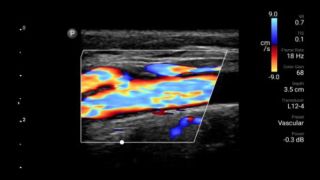

Decrease complications of CVC insertions

Real-time ultrasound guidance can improve the accuracy and safety of CVC insertions.

Lumify L12-4 broadband linear array transducer

• 12 to 4 MHz extended operating frequency range • Aperture size: 34mm • 2D, steerable color Doppler, M-mode, advanced XRES and multivariate harmonic imaging, SonoCT • High resolution imaging for shallow applications: soft tissue, vascular, superficial, musculoskeletal, and lung • Center line marker • USB-C transducer with replaceable cable